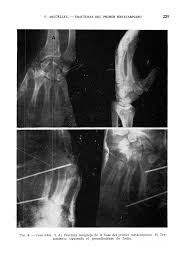

Fractura luxación de la base del 1er metacarpiano.

Fractura luxación de la base del 1er metacarpiano. Es la fractura que se extiende a través de la base del metacarpiano del pulgar hasta la articulación carpometacrpiana, con desplazamiento del metacarpiano en relación con el trapecio.

Mediante la radiografía se observa que hay una fractura oblicua a través de la base del metacarpiano, y que el fragmento diafisario o distal está desplazado hacia arriba y hacia atrás, lo cual hace que el fragmento proximal interno se mantenga sin desplazamiento.